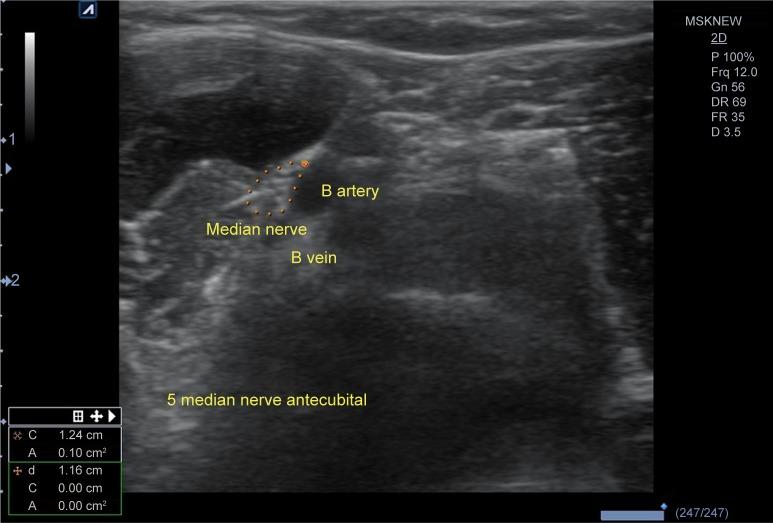

Individuals with upper limb complaints and reference subjects were recruited from the Rofaydeh Hospital, Tehran, Iran, from June 2013 to October 2014 - (15 months). We evaluate case and control subjects for health status, demographics, clinical characteristics of CTS, median nerve physiology by electrodiagnostic tests, and anatomy by US. Median nerve cross-sectional area (CSA) at precanal, tunnel inlet, midcanal, tunnel outlet, and antecubital levels was measured applying US examination.

我们从 2013 年 6 月至 2014 年 10 月(15 个月)在伊朗德黑兰的 Rofaydeh 医院招募了上肢有症状的患者和参考对象。我们评估了病例组和对照组的健康状况、人口统计学特征、CTS 的临床特征、电诊断测试中的正中神经生理学以及 US 下的解剖结构。在预管、管入口、中管、管出口和肘前水平测量正中神经横截面积(CSA)。